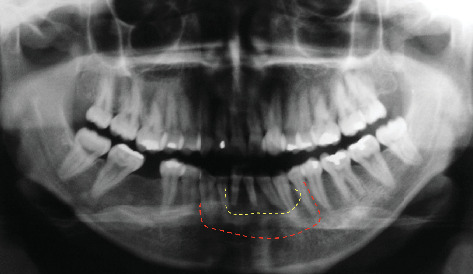

目的:本病例报告详细介绍了一名28岁女性前下颌弓复发性中央巨细胞肉芽肿(CGCG)的长期治疗。病例报告:在2007年首次手术切除后,导致明显的骨缺损,采用多学科方法恢复下颌完整性和功能。2009年,使用DePuy Synthes牙槽牵张器进行牙槽牵张成骨。随后,在2011年进行了自体上牙体植骨,以优化牙槽嵴轮廓。2012年放置了4个Neodent CM植入物,随后进行了假肢康复。2024年的15年随访显示了良好的结果,种植体周围组织稳定,骨水平维持正常,假体功能齐全。本病例强调了包括牵张成骨和自体植骨在内的先进手术技术在治疗复杂CGCG病例中的疗效。结果和结论:成功的长期结果强调了综合治疗方法和定期随访对解决侵袭性和复发性cgcg带来的挑战的重要性。本报告提供了有价值的见解,在广泛的CGCG治疗后,全面功能和美学修复的潜力,强调了在颌面重建中良好协调的多学科方法的好处。

Aim: This case report details the long-term management of a recurrent central giant cell granuloma (CGCG) in the anterior mandibular arch of a 28-year-old female. Case Report: Following initial surgical resection in 2007, which resulted in a significant bony defect, a multidisciplinary approach was employed to restore mandibular integrity and function. In 2009, alveolar distraction osteogenesis was performed using a DePuy Synthes alveolar distractor. Subsequently, in 2011, autogenous onlay bone grafting was carried out to optimize the alveolar ridge contour. Four Neodent CM implants were placed in 2012, followed by prosthetic rehabilitation. The 15-year follow-up in 2024 revealed excellent outcomes, with stable peri-implant tissues, maintained bone levels, and a fully functional prosthesis. This case highlights the efficacy of combining advanced surgical techniques, including distraction osteogenesis and autogenous bone grafting, in managing complex CGCG cases. Results and Conclusion: The successful long-term outcome underscores the importance of a comprehensive treatment approach and regular follow-up in addressing the challenges posed by aggressive and recurrent CGCGs. This report provides valuable insights into the potential for fully functional and aesthetic restoration following extensive CGCG treatment, emphasizing the benefits of a well-coordinated, multidisciplinary approach in maxillofacial reconstruction.